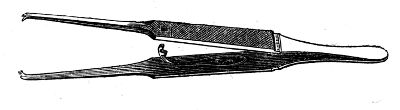

Attention to the apparatus is necessary. It should be in good order,